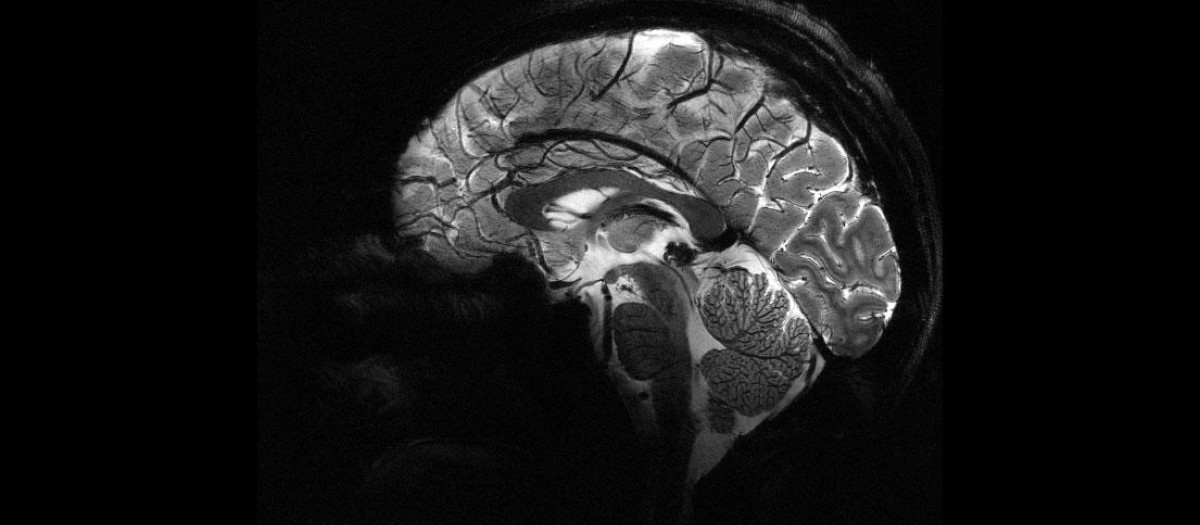

Imagen lateral del cerebro

Cuatro minutos y la mejor máquina de resonancia magnética del mundo. Esto es lo único que se necesita para tener una de las imágenes cerebrales más claras y completas del mundo. Un equipo de investigadores de la Comisión de Energía Atómica de Francia (CEA) ha logrado por primera vez en la historia captar en una resolución muy detallada el plan de uno de los órganos más importantes del cuerpo humano.

Este nuevo hallazgo, llevado a cabo gracias a la máquina de resonancia magnética Iseutl –la más potente hasta la fecha–permitirá a los científicos obtener información antes inalcanzable sobre los mecanismos cerebrales. También les ayudará a comprender cómo el cerebro codifica las representaciones mentales y descubrir qué firmas neuronales están asociadas con el estado de conciencia.

En solo cuatro minutos, el escáner, que utiliza tecnología de imágenes por resonancia magnética y tiene una intensidad de campo magnético de 11,7 teslas, ha sido capaz de captar las imágenes más destalladas y espectaculares de todos los tiempos. Estas tienen una resolución impecable para un tiempo de adquisición tan corto: resolución en el plano de 0,2 milímetros y grosor de corte de 1 milímetro, lo que representa «un volumen equivalente a unos pocos miles de neuronas», han señalado.